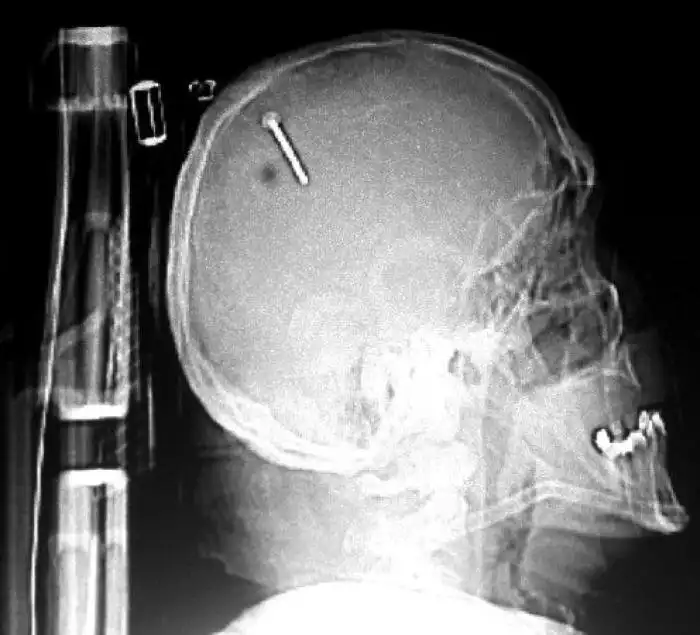

Необычные предметы в теле людей на рентгеновских снимках

На рентгеновских снимках людей порой можно обнаружить самые необычные предметы, которые находятся в их теле.